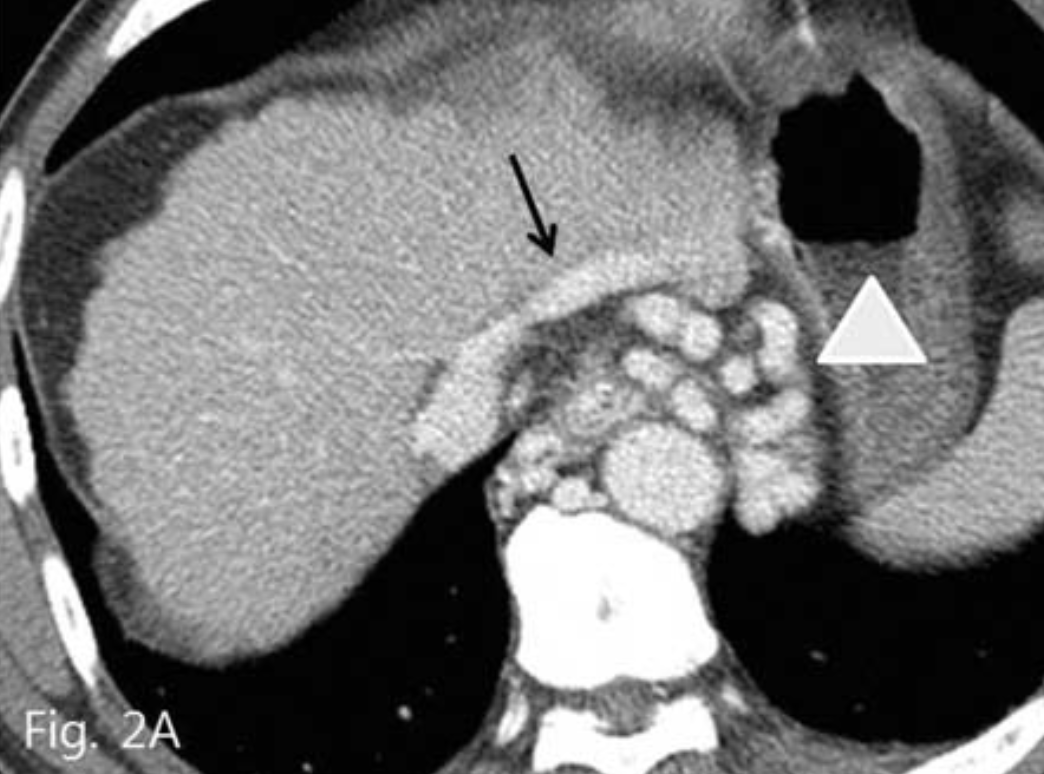

복부 전산화 단층촬영(CT)에서 간경화 및 비장비대의 소견과 함께 위식도 정맥류가 관찰되었다. 위정맥류의 경우 위신 단락 (gastrorenal shunt)은 보이지 않았으며, 대신 현저하게 늘어나 있는 위하대정맥 단락 (gastrocaval shunt)이 확인되었고 이것이 위정맥류의 주 유출정맥으로 생각되었다(Fig. 2A-C).

Fig. 2

Contrast enhanced CT (A~C) shows esophageal and gastric varices (arrowhead) and gastrocaval shunt (arrow).